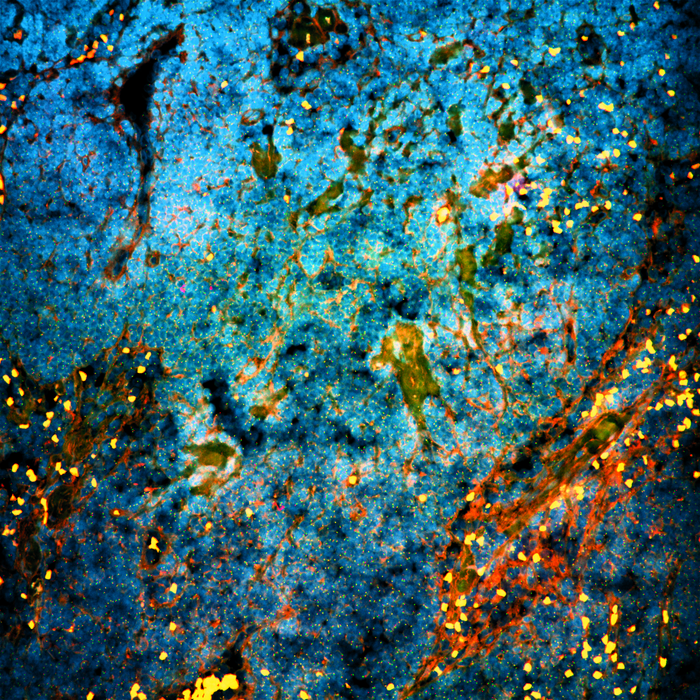

An international research team led by scientists from the Netherlands Cancer Institute and Oncode Institute has made a surprising discovery using tissue from patients with prostate cancer who had been treated with testosterone-inhibiting drugs. They discovered that an unexpected class of proteins, namely proteins that normally regulate the circadian clock, dampens the effects of the anti-hormonal therapy. ‘Prostate cancer cells no longer have a circadian rhythm,’ says Wilbert Zwart, one of the research leaders. ‘But these 'circadian clock' proteins acquire an entirely new function in the tumor cells upon hormonal therapy: they keep these cancer cells alive, despite treatment. This has

The study was based on tissue from 56 patients with high-risk prostate cancer, who had received three months of anti-hormonal therapy before their surgery. After those three months, their tissue was examined at the DNA level. 'We noticed that the genes keeping the tumor cells alive despite the treatment, were suddenly controlled by a protein that normally regulates the circadian clock,' says researcher Simon Linder, who will receive his PhD for his research in this study. This surprising discovery also creates new opportunities, because inhibition of this circadian protein was found to further increase sensitivity to anti-hormonal therapy in prostate tumor cells in the lab as well as in mice.